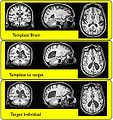

We are developing an ANTS-based registration module.

Our approach for implementing ANTS registration will be to create a command line module and integrate ANTS into the Slicer build process, if possible.